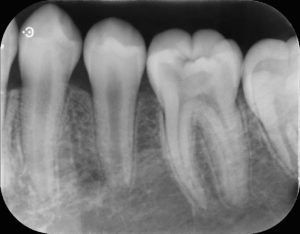

所見:左下第一大臼歯に歯髄に近接した大きなう蝕をみとめる。自発痛などの症状はない。う蝕を除去する際に歯髄が露出する可能性が高い。

通常の治療では根管治療により歯髄を除去することが考えられる状況であるが、臨床症状がなく、年齢も若い子とから歯髄温存療法を行うこととした。

若年性のう蝕は急性う蝕といい進行が早いため、処置が遅れると根管治療が必要となることがあります。なかなか自覚症状も出ないため本人には気づきにくいことがよくあります。